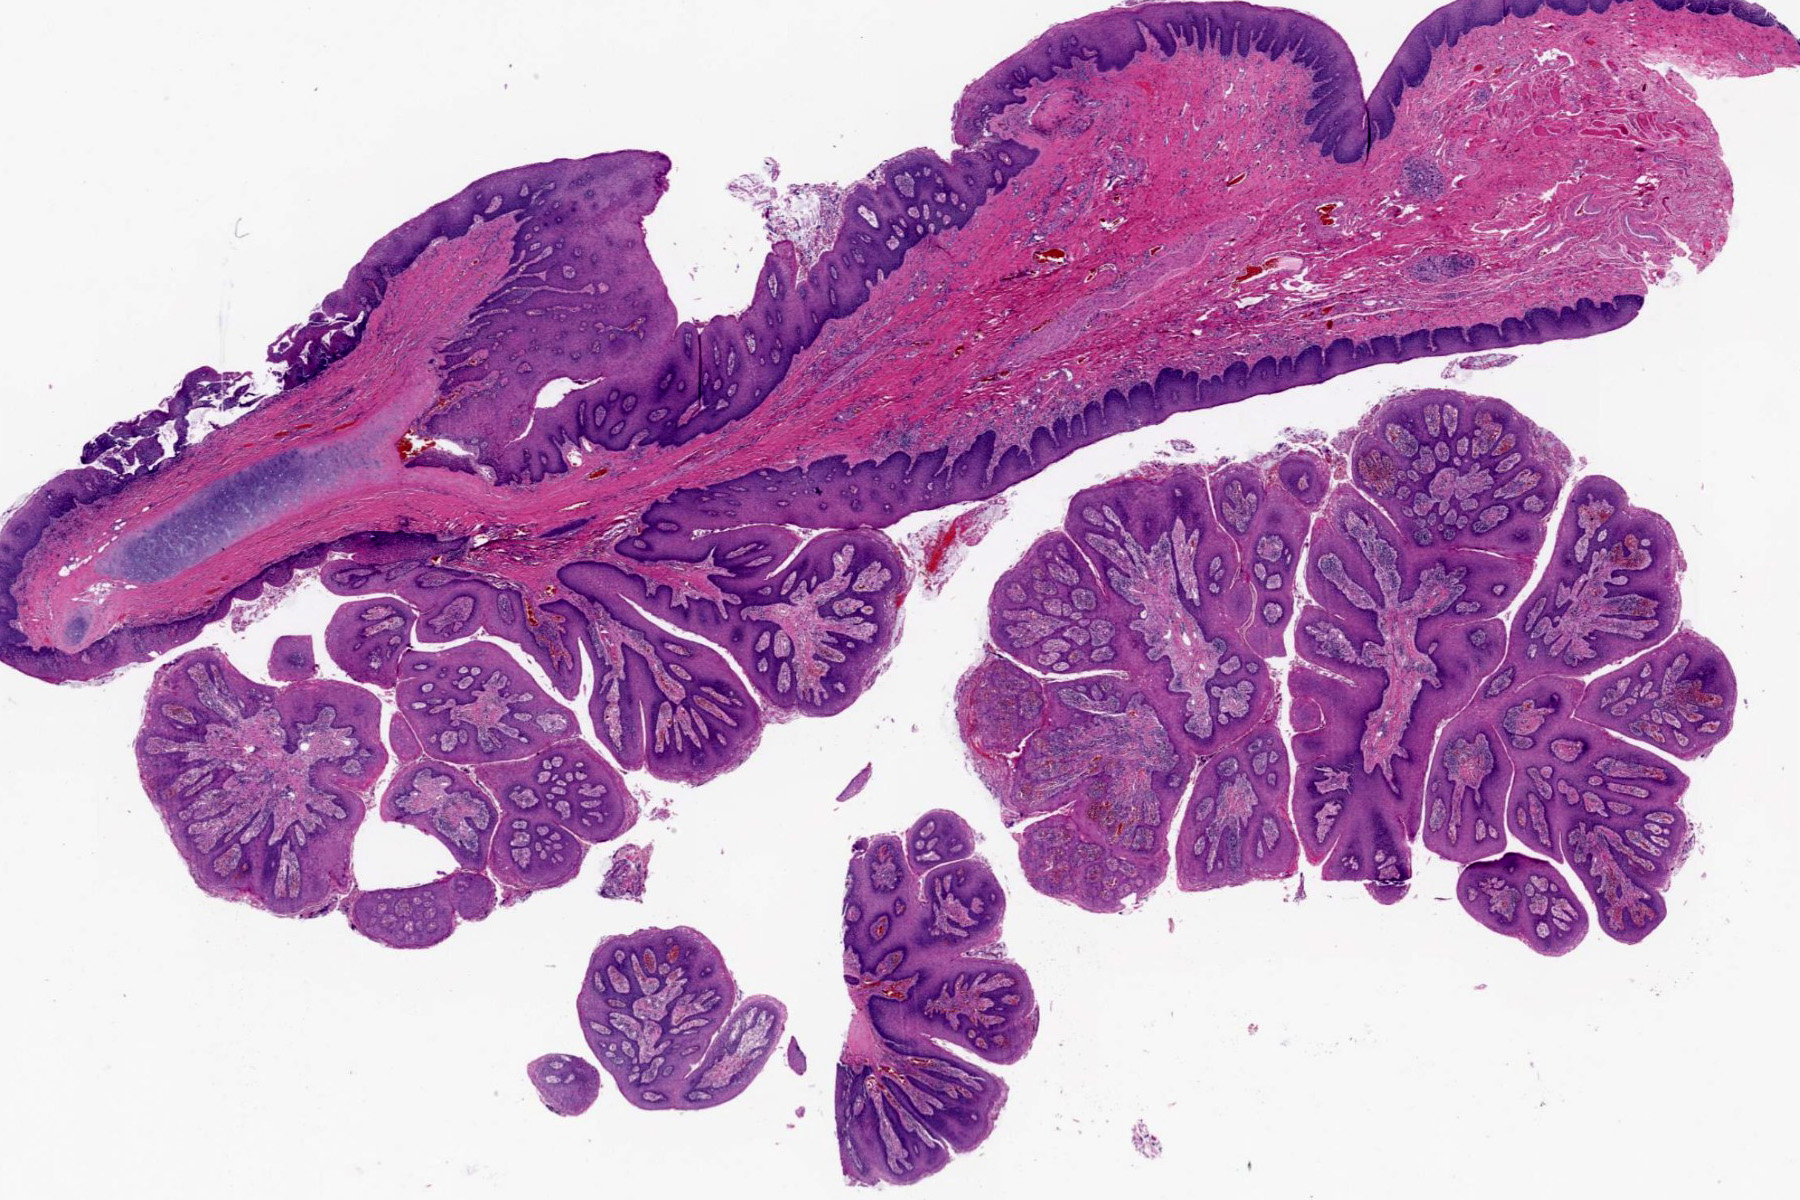

Microscopic (histologic) description

- Finger-like projections or multiple fronds with a central fibrovascular core, covered by benign hyperplastic stratified squamous epithelium

- Basal and parabasal hyperplasia

- Increased mitotic figures in the basal and parabasal layers

- Koilocytic changes in upper layer: may be pronounced or subtle

- Surface keratinization: absent to minimal

Microscopic (histologic) images